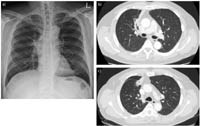

Hình 4 (a) Hình chụp X-quang ngực theo hướng từ sau ra trước cho thấy có sự bất thường của rốn phổi bên phải ở một bệnh nhân nhiễm sán lá phổi Paragonimusspp.

(b) Hình ảnh CT cho thấy có một khu vực mô phổi bị hoại tử và phế quản bị tắc nghẽn ở phân đoạn trước của thùy trên bên phải.

Điều này có thể là dấu hiệu của các loại nhiễm trùng hoặc viêm như lao, actinomycosis, viêm phổi và ít có khả năng là ung thư phổi ở cùng bệnh nhân nhiễm sán lá phổi Paragonimus spp.

(c) Hình chụp CT ngực theo dõi sau 8 tháng điều trị bằng kháng sinh và liệu pháp kháng nấm không thấy dấu hiệu

cải thiện và bệnh nhân có dấu hiệu hình thành khoang trong phổi.